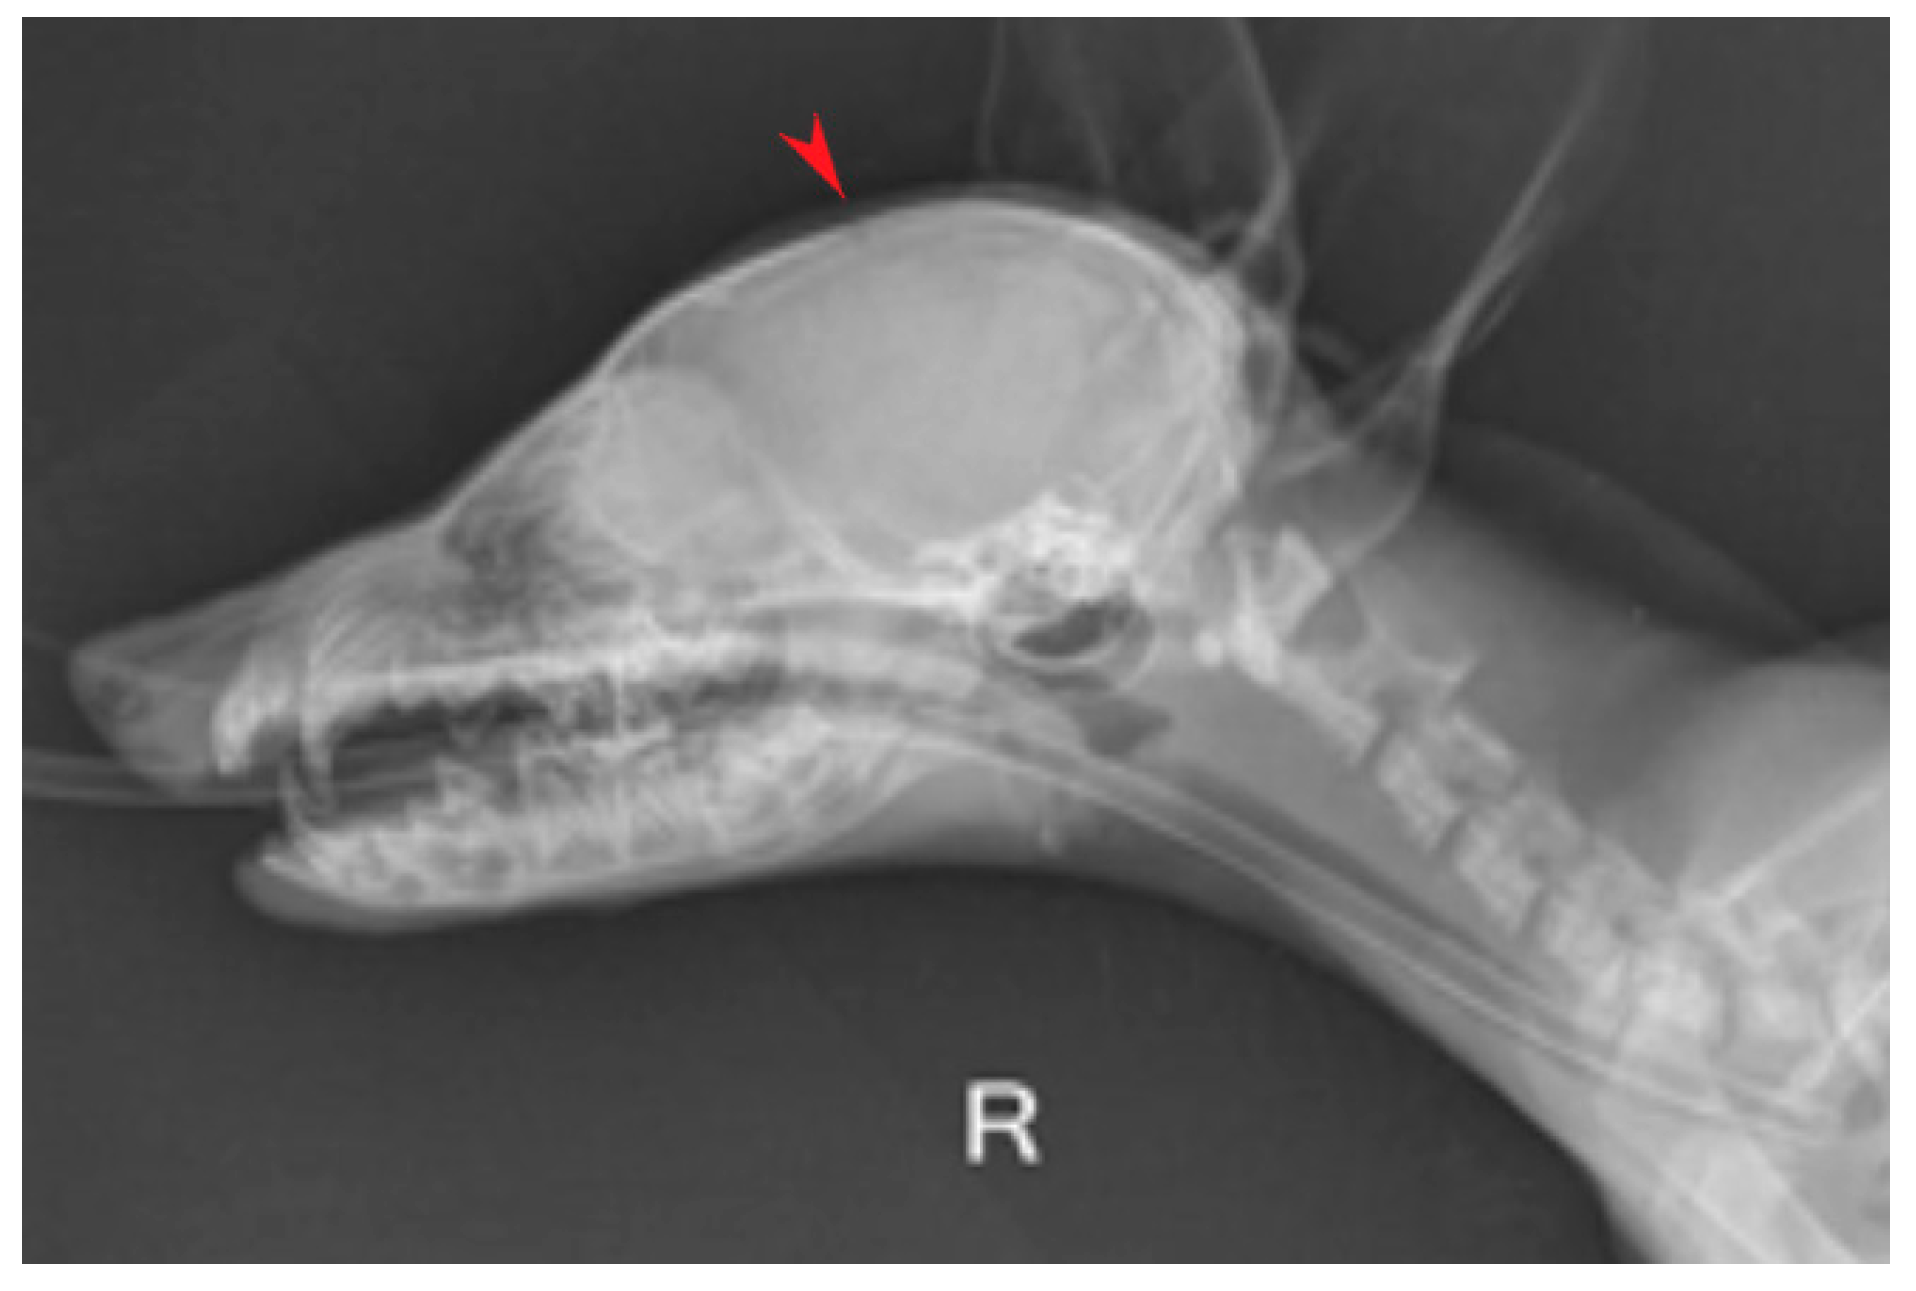

Imaging Diagnosis of Hydrocephalus in a Fox Cub-Case Study

2. Case Description